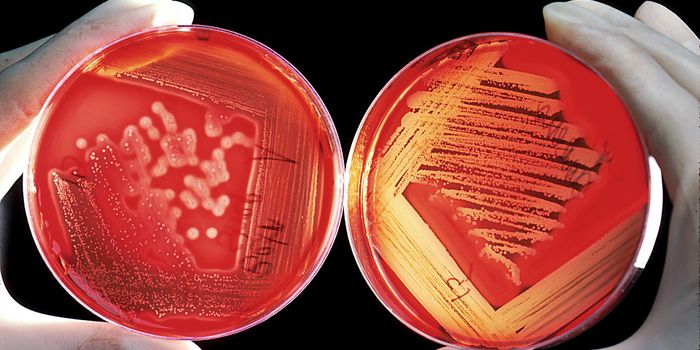

MAR 19, 2017MicrobiologyIt can be incredibly challenging to give a patient the proper treatment when they are infected by an antibiotic-resistan ...